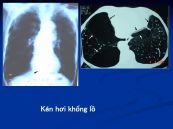

Kén hơi khổng lồ phổi trái gây cản trở chức năng của phổi; nó có thể gây áp lực lên phổi và gây trở ngại cho chức năng thích hợp của nó. Cùng eLip tham khảo ngay bài viết dưới đây để hiểu rõ hơn về hội chứng này nhé!

Khí phế thũng gây mất tính đàn hồi thành của các túi khí nhỏ trong phổi. Cuối cùng, thành của các túi căng và không co lại, mà tạo ra kén lớn hơn. Để biết rõ hơn về hội chứng này, mời các bạn cùng tham khảo bài viết ngay dưới đây!